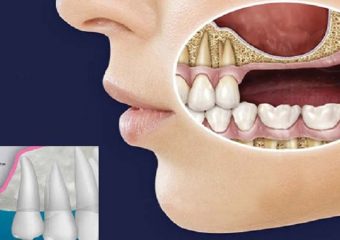

جراحی سینوس لیفت چگونه انجام میشود؟

جراحی سینوس لیفت چگونه انجام میشود؟

اکنون، آنچه را که میتوانید از این جراحی انتظار داشته باشید را مرور خواهیم کرد تا هنگام انجام سینوس لیفت، کاملاً آماده و مطمئن باشید. در اینجا یک چشمانداز کلی از وقایعِ رخ داده در حین جراحی سینوس لیفت را مشاهده خواهید کرد:

- جراح بافت لثه را برش میدهد.

- بافت را بالا برده و استخوان زیر آن را در معرض قرار میدهد.

- جراح استخوان را به اندازهی یک دایره کوچک برش میدهد.

- جراح قطعهی استخوانی را درون فضای حفرهی سینوس بالا میآورد و سوراخ را با یک پیوند استخوان پر میکند.

- جراح محل برش را میبندد.

- روند بهبودی آغاز میشود.

در حدود ۴ تا ۱۲ ماه پس از جراحی سینوس لیفت، دندانپزشک ایمپلنتهای شما را قرار میدهد. این مدت زمان ۴ تا ۱۲ ماهه به استخوان جدید زمان میدهد تا به درستی با استخوان موجود شما ادغام شود. مدت زمان بین جراحی و قرار دادن ایمپلنت به میزان استخوان مورد نیاز شما بستگی دارد. متخصص دندانپزشکی به شما اطلاع میدهد که چه زمانی قادر به انجام ایمپلنت شما است.